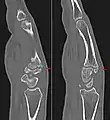

The joint between the index metacarpal and the capitate is a fibrous non-mobile joint. Some people have a gene that leads to this growth. It looks like arthritis (bone spurs on each side of the joint) on X-ray. It looks like a ganglion on the hand, but more towards the fingertips.

Carpometacarpal boss is uncommon and there is not much scientific data. Its etiology has yet to be fully defined, but can be congenital in the form of an accessory ossicle (os styloideum) or may be acquired from trauma, repetitive use, or degenerative osteophytosis.[3] The condition usually begins to show in the 3rd or 4th decade.

1. Conway, William F.; et al. (1984). "The Carpal Boss: An Overview of Radiographic Evaluation" (PDF). Radiology. 156 (1): 29–31. doi:10.1148/radiology.156.1.3923555. PMID 3923555. Retrieved 27 July 2020.

3. Conway, W.F. "The carpal boss: an overview of radiographic evaluation". Radiological Society of North American. Retrieved April 13, 2020.